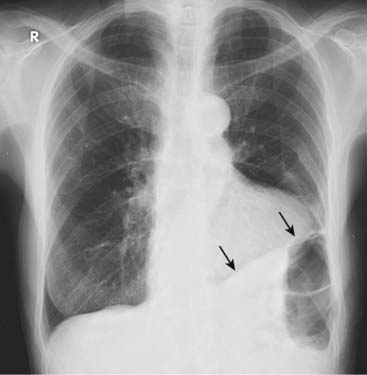

Figure 6-10 Large left pleural effusion.

The left hemithorax is completely opacified, and the mobile mediastinal structures such as the trachea (solid black arrow) and the heart (dotted black arrow) have shifted away from the side of opacification. This is characteristic of a large pleural effusion, which acts like a mass. In most adults, about 2 L of fluid is required to fill or almost fill the entire hemithorax such as this.